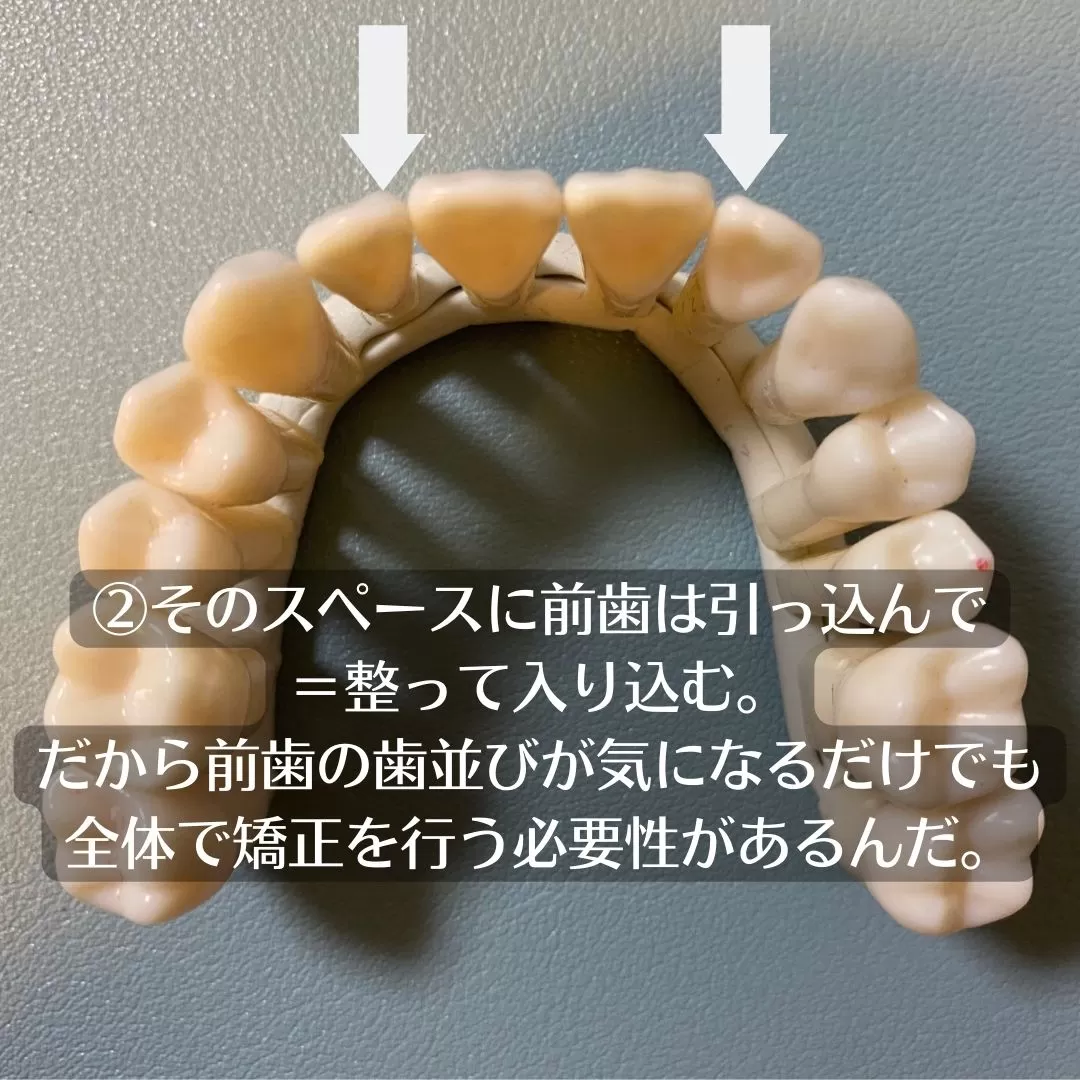

しかしながらこちらはこのように治したのですが

並んでおりますが、並べるというよりも、整えるという感性で考えると

少々方法論が変わります。

【拡大】ということをしています。

歯の軸を起こしましてスペースを作るのです。

奥歯の噛み合わせの位置が変わるので、奥からの治療となり

全体での歯列矯正となります。